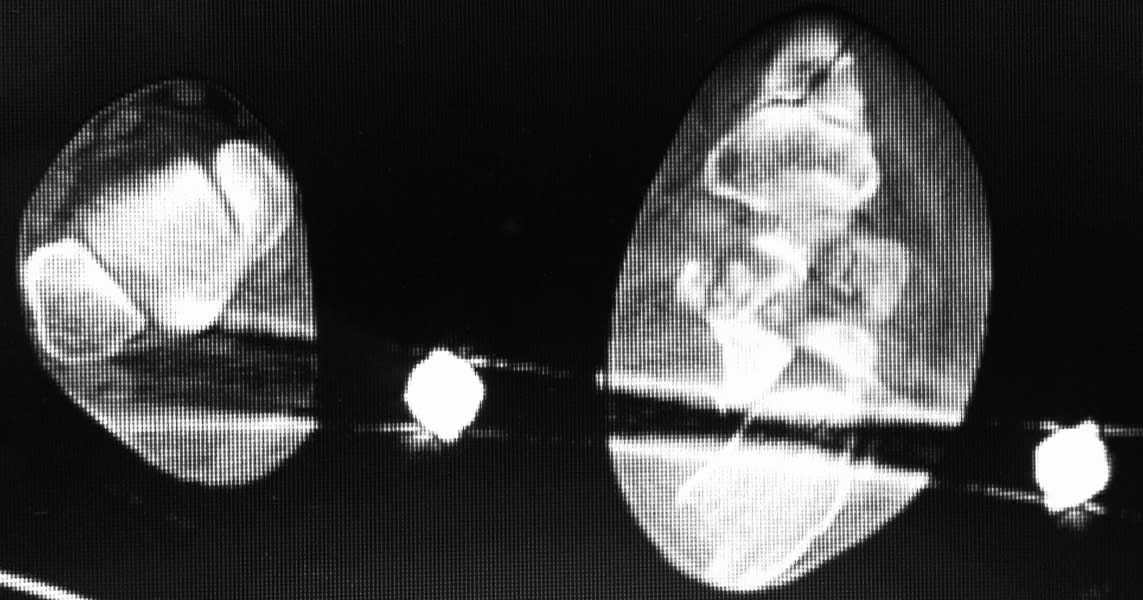

немного КТ

На аппарате к сожалению не возможно провести репазицию отломков при оскольчатых переломах пятки. Единственное что вы добетесь это востановите свод стопы. Так как поциент молодой я всётаки склонен к открытому методу используя специальную пластину. Во время операции будте внимательны к мягким тканям.